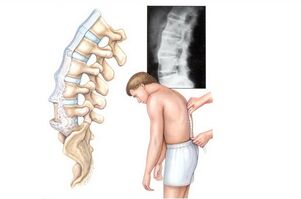

- omurganın her türlü eğriliği ve bunların kombinasyonu, torasik omurgada bir "tümsek" görünümüne neden olan deformite dahil;

İleri vakalarda, omurganın ciddi bir eğriliğini dışlamayan yüksek bir komplikasyon olasılığı vardır.